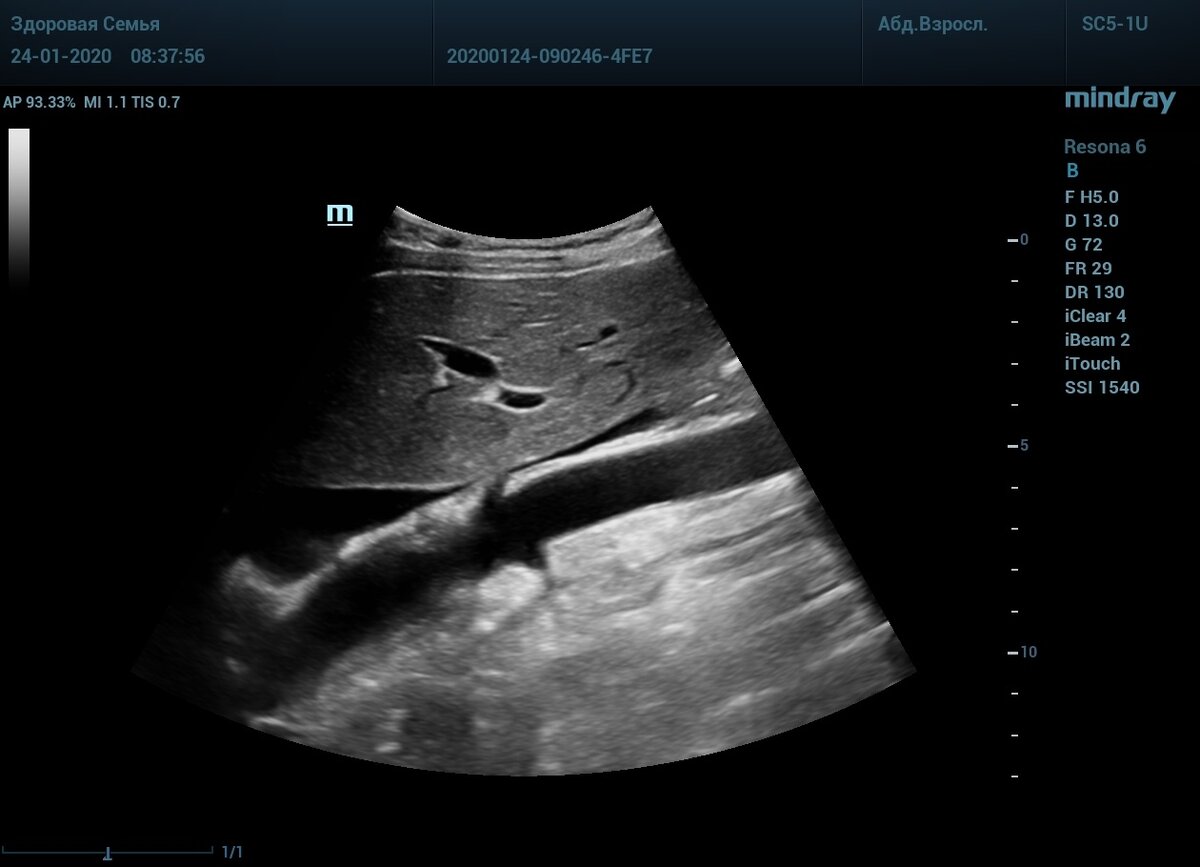

Истоки почечных артерий

🍌Банана челендж, версия для ультразвука :)

🧐Сложной техникой считается получение продольного среза истока почечных артерий, того самого места где растут бляшки.

❕Требования: продольно аорта, почечные артерии как будто кожура банана отгибаются в стороны. Только так можно узнать истинную скорость кровотока в истоке.

➡️Стрелочками указаны истоки - кожура банана.